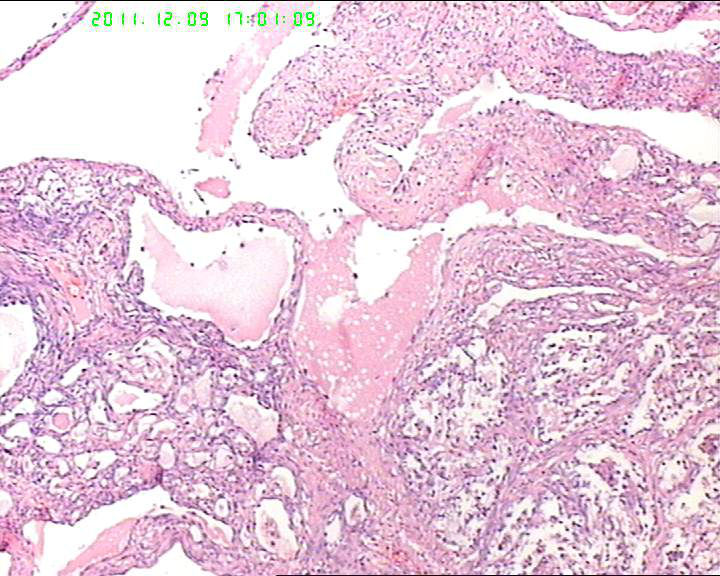

盆腔包块4个月,13*8*7cm 大小,囊实性,实性区菜花状、灰白质脆,局部半透明。

筛状迷路样结构,部分呈乳头状,异型明显,S-D小体不明显,考虑卵黄囊瘤。做CK,AFP,AAT.

首先考虑透明细胞癌,鉴别卵黄囊瘤

有腺腔样结构,内衬靴钉样细胞,还可见透明细胞,首先考虑透明细胞癌,鉴别诊断:内胚窦瘤。内胚窦瘤的网状结构内衬是扁平的上皮。

肿瘤细胞弥漫性生长,细胞排列成腺样、腺泡状,细胞异型明显。突向腔内。

卵巢生殖细胞肿瘤,卵黄囊瘤;

性索间质肿瘤,颗粒细胞瘤;

转移性的癌

有鞋钉样细胞,首先考虑透明细胞癌。要除外卵黄囊瘤,浆乳癌。